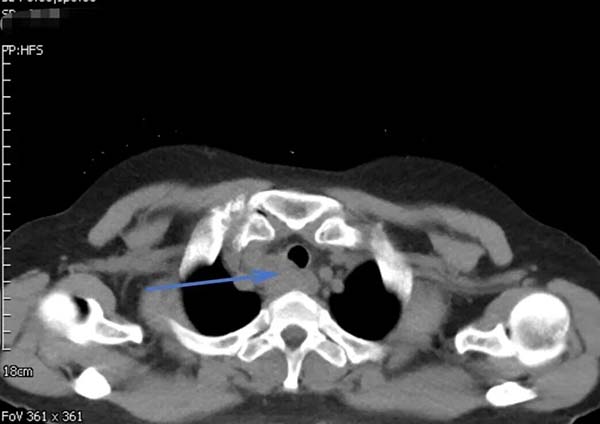

62岁的郑女士近一月来进食时总有食物下咽不畅感,伴有明显哽咽。当地医院胸部增强CT提示食管上段有一约3.7×2.6CM占位性病变,影像报告“不除外食管癌,且可能累及气管后壁”。随后的PET-CT更显示该病灶糖代谢异常增高,代谢活性值高达14.4,强烈指向恶性肿瘤可能。这一系列检查结果让患者及家人陷入焦虑与恐惧。

▲治疗前胸部CT